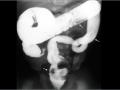

Hemorragia adrenal em recém nascido

Set de 2024.

2.742